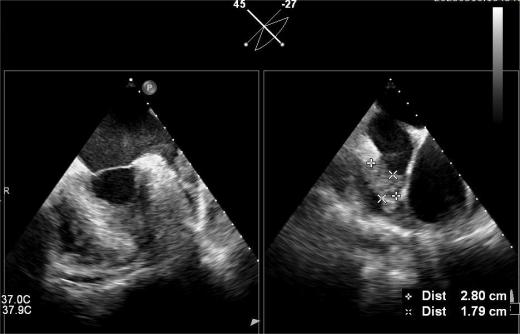

▲血栓位于心耳中段

其中首场公开演示的左心耳血栓封堵病例拥有极高难度,患者术前TEE显示左心耳血栓形成伴机化,血栓位于心耳中段,近中端絮状物显著。封堵机遇只有一次,选型和操作稍有失误,城市增长手术风险。因而手术采取全麻,并装置了抗栓塞脑动脉;ぷ爸,以削减术中风险。通过TEE疏导下丈量左心耳大幼以及确认左心耳血栓地位,李岳春教授凭借自身丰硕经验最终决定使用LAmbre 2632型号,选取推送式植入法将左心耳血栓牢牢锁死于远端,并且封堵器一次成型,封堵成效极佳,实现后取出脑;ぷ爸,均未见血栓,顺利实现了此台高难度的手术,获得了学员们的一致认可。